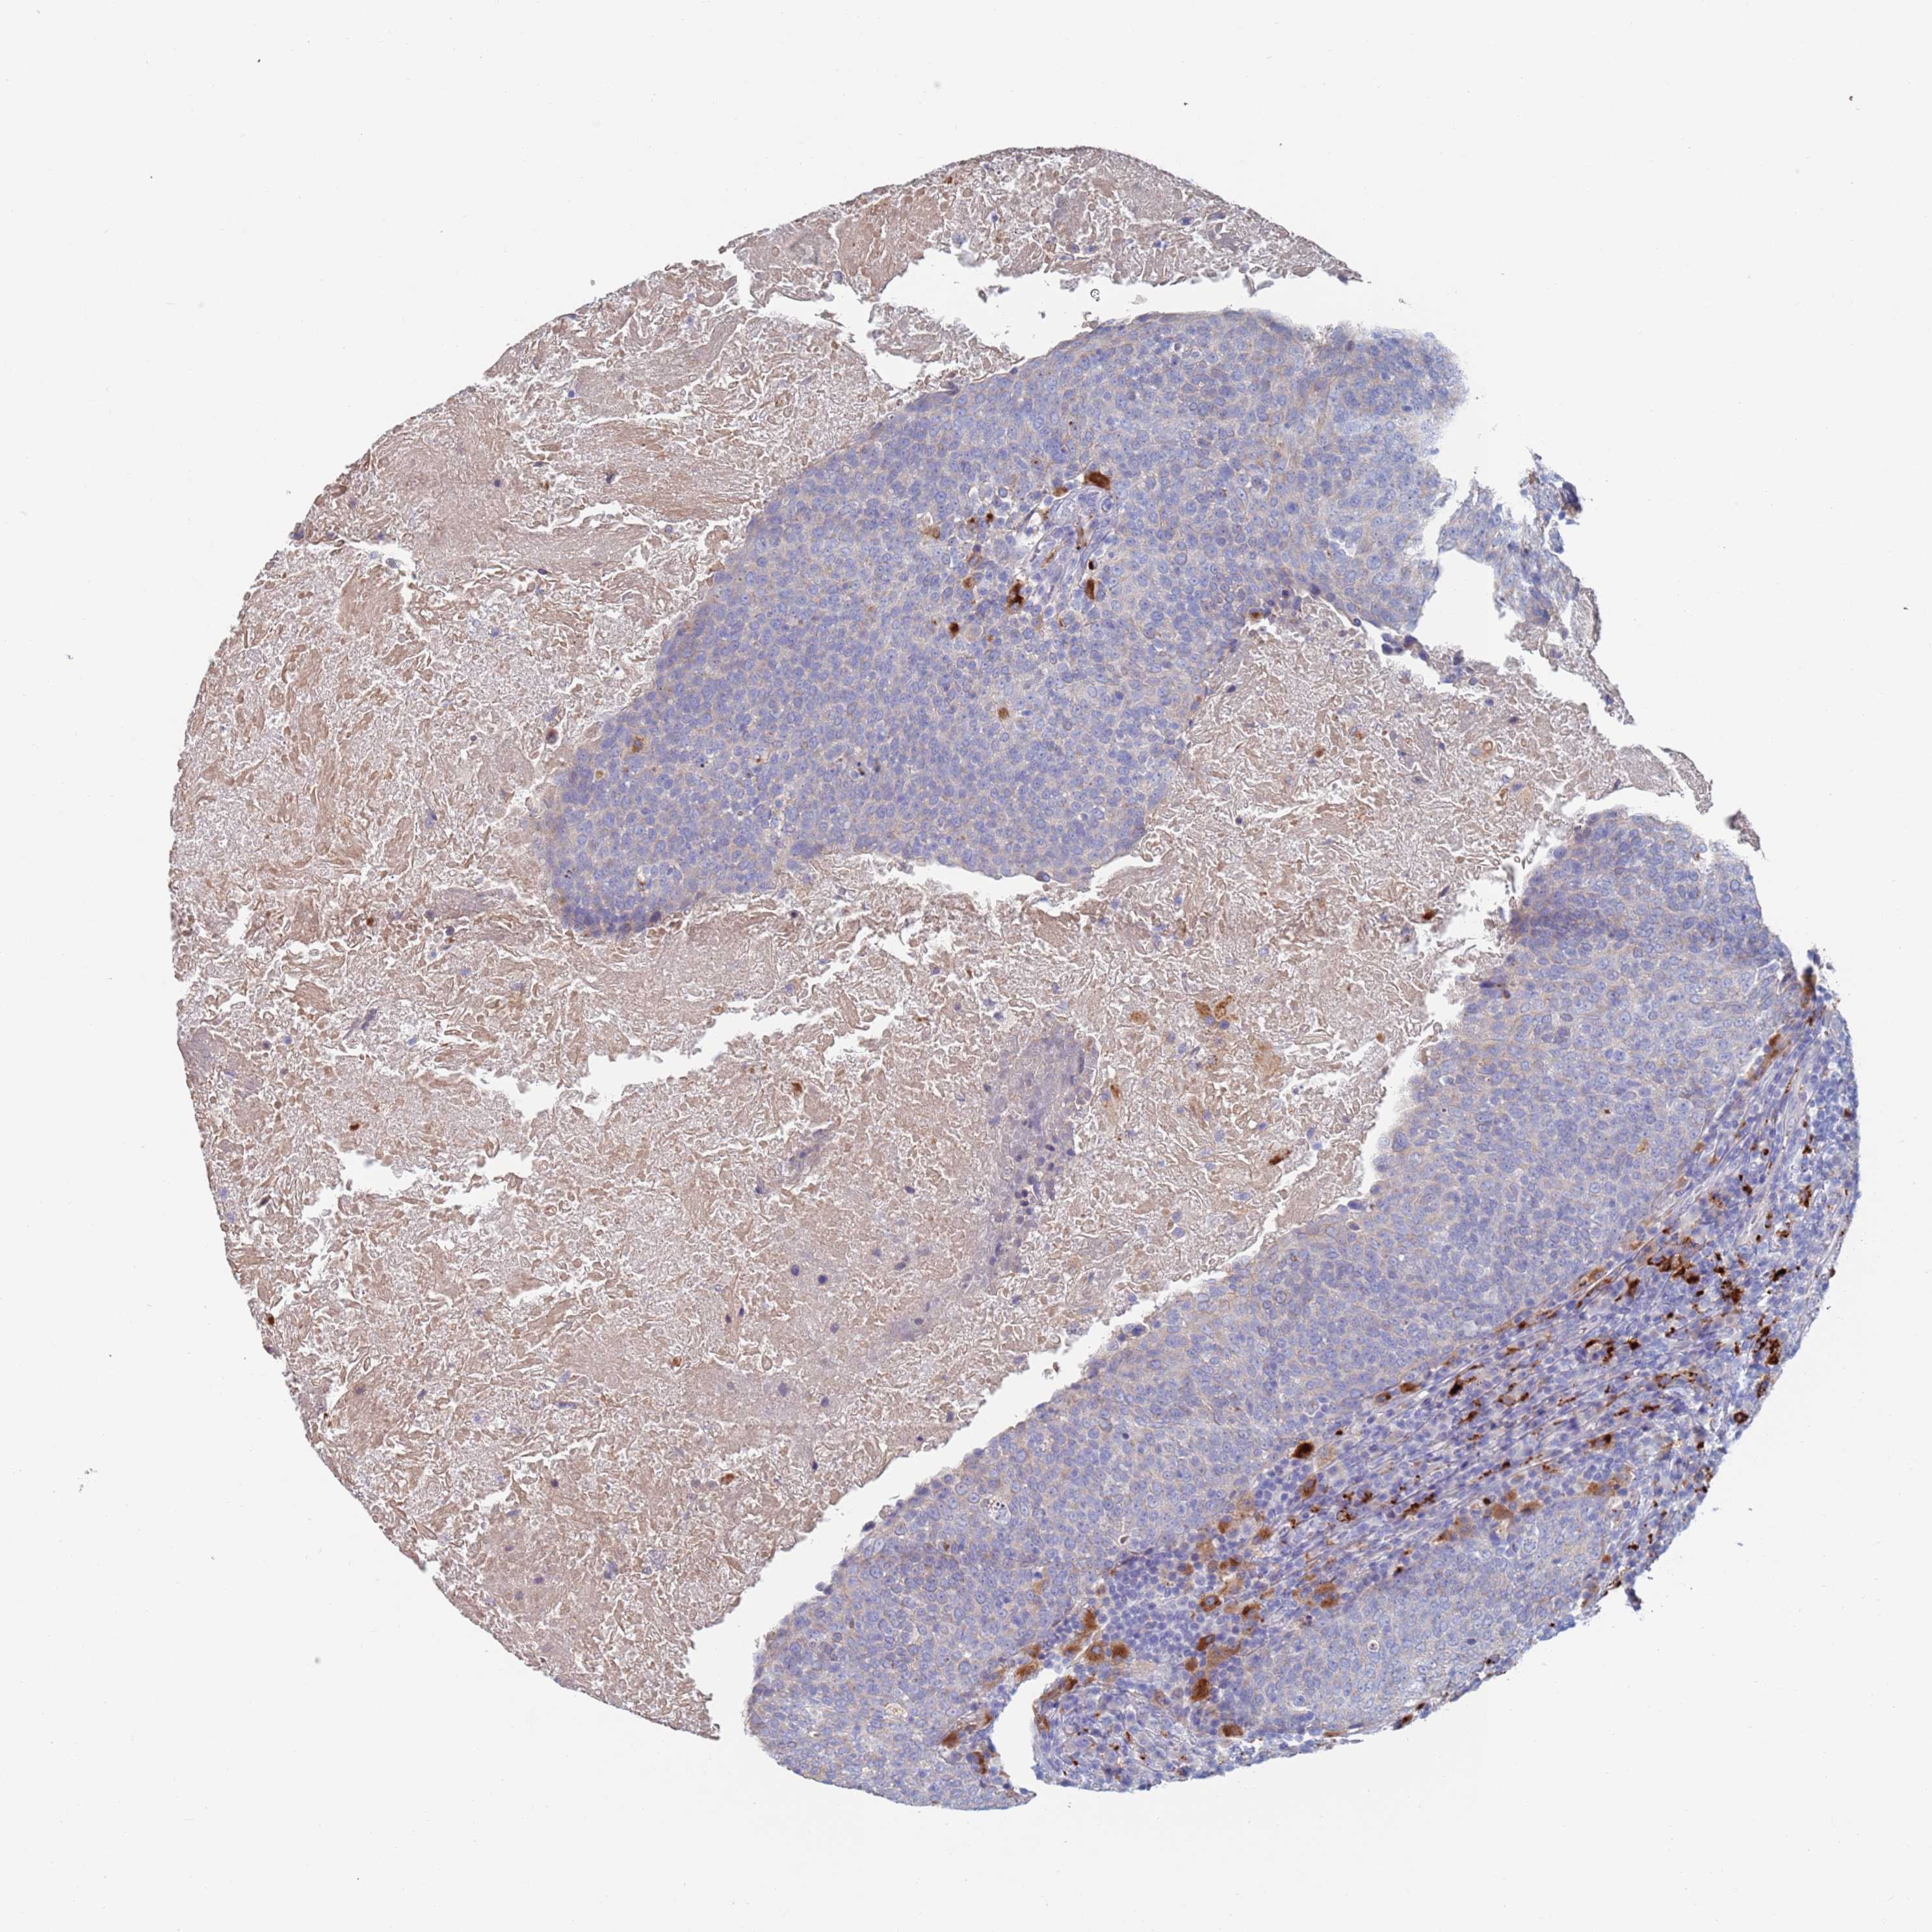

HEAD AND NECK CANCER - Protein expressioni

A mouse-over function shows sample information and annotation data. Click on an image to view it in a full screen mode. Samples can be filtered based on level of antibody staining by selecting one or several of the following categories: high, medium, low and not detected. The assay and annotation is described here.

Antibody stainingi

Antibody staining in the annotated cell types in the current human tissue is reported as not detected, low, medium, or high, based on conventional immunohistochemistry profiling in selected tissues. This score is based on the combination of the staining intensity and fraction of stained cells.

Each image is clickable and will lead to virtual microscopy that enables deeper exploration of all samples and also displays staining intensity scores, fraction scores and subcellular localization as well as patient and tissue information for each sample.

Antibody HPA046542

Staining

High

Medium

Low

Not detected

Intensity

Strong

Moderate

Weak

Negative

Quantity

>75%

75%-25%

<25%

None

Location

Nuclear

Cytoplasmic/membranous

Cytoplasmic/membranous,nuclear

Squamous cell carcinoma, NOS